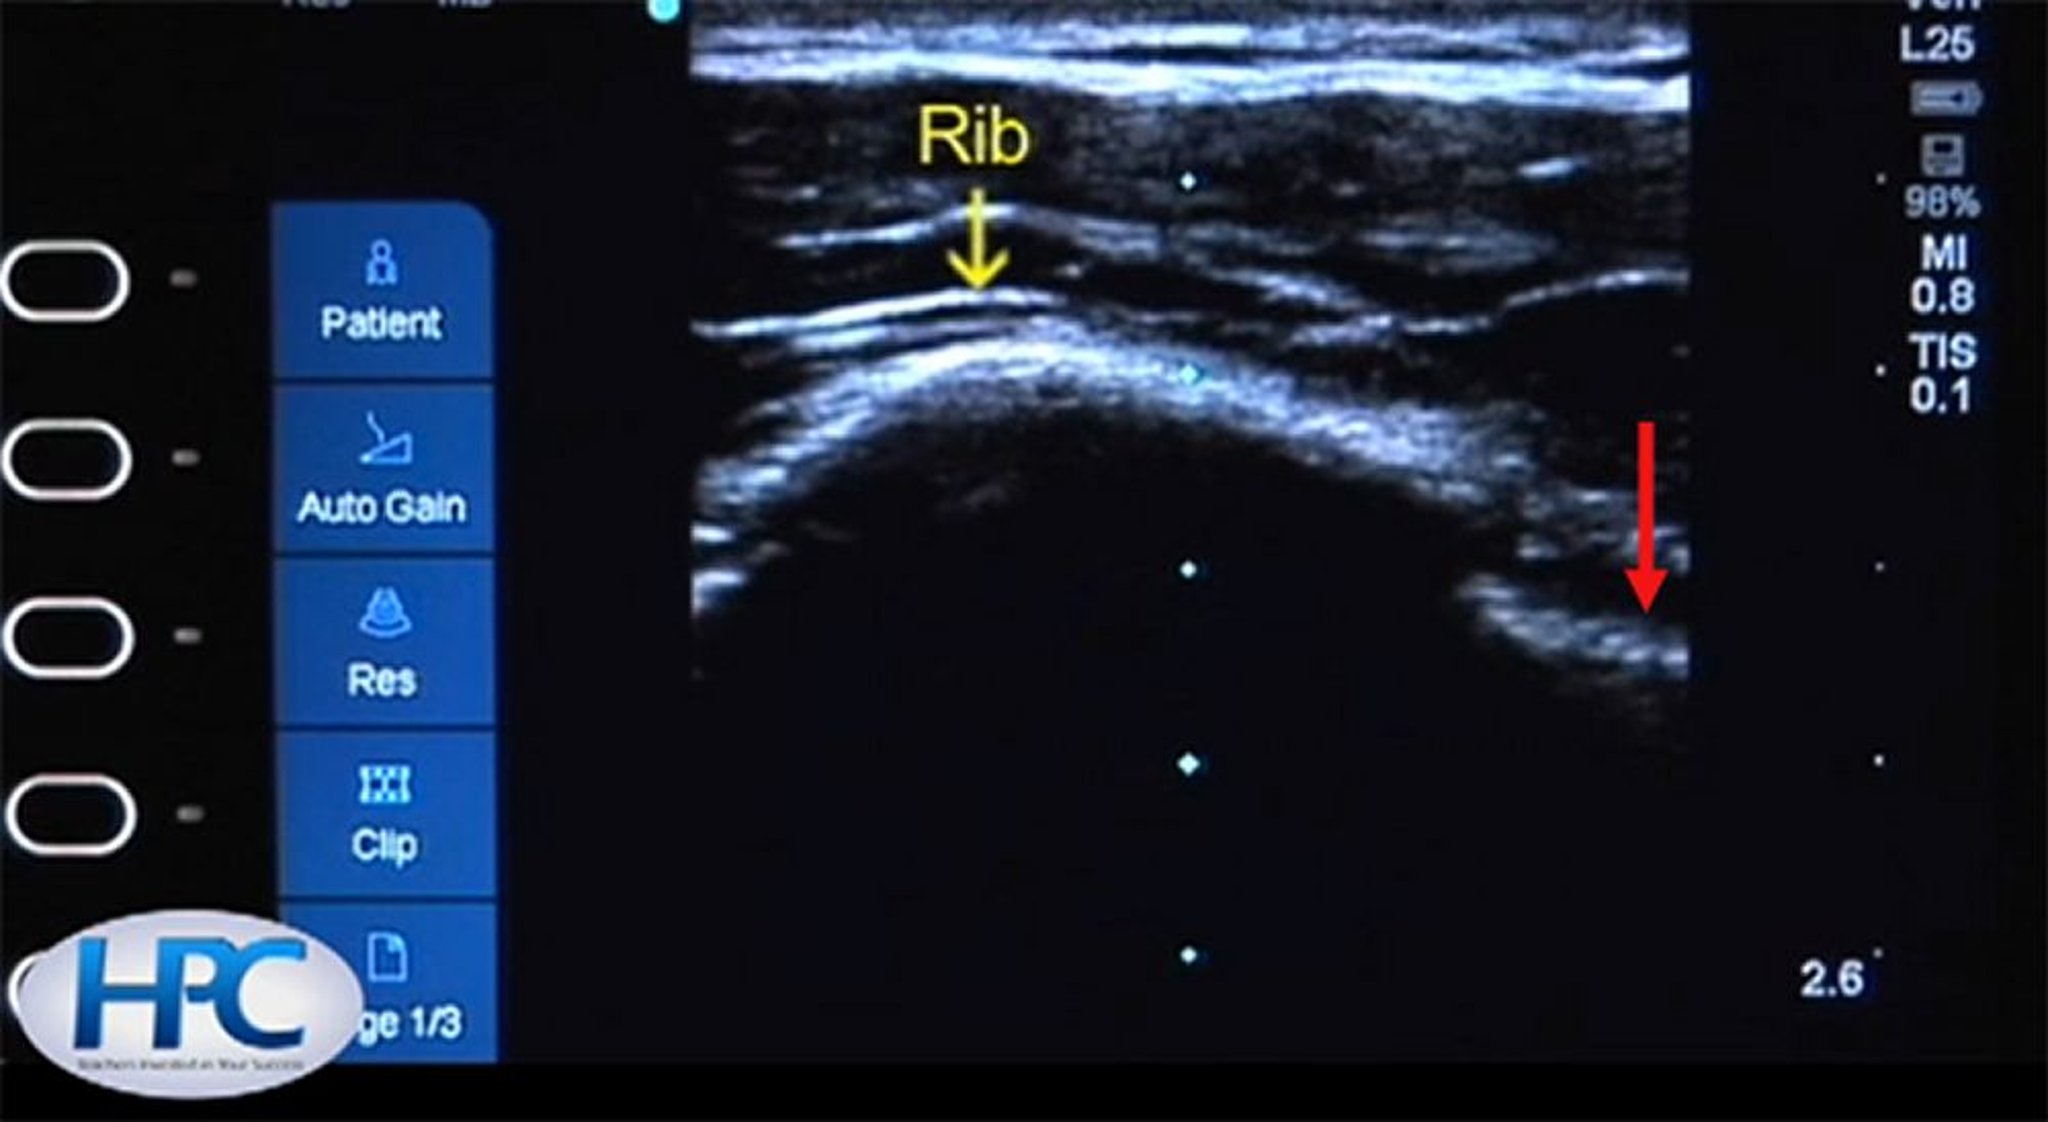

Aspecto ecográfico de las costillas y la línea pleural

La costilla (flecha amarilla) aparece como una estructura hiperecogénica (blanca) con sombra acústica debajo de la costilla. La línea pleural (flecha roja) es visible en el espacio intercostal.